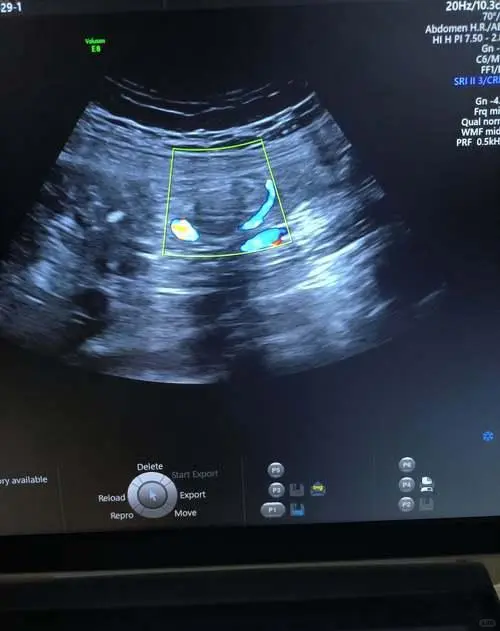

7. 腹部彩超

检查肝、胆、脾、胰、肾等脏器是否有囊肿、结石、占位病变